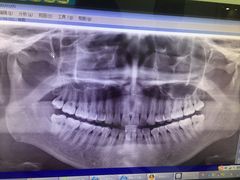

• 德伦口腔

• -德伦口腔